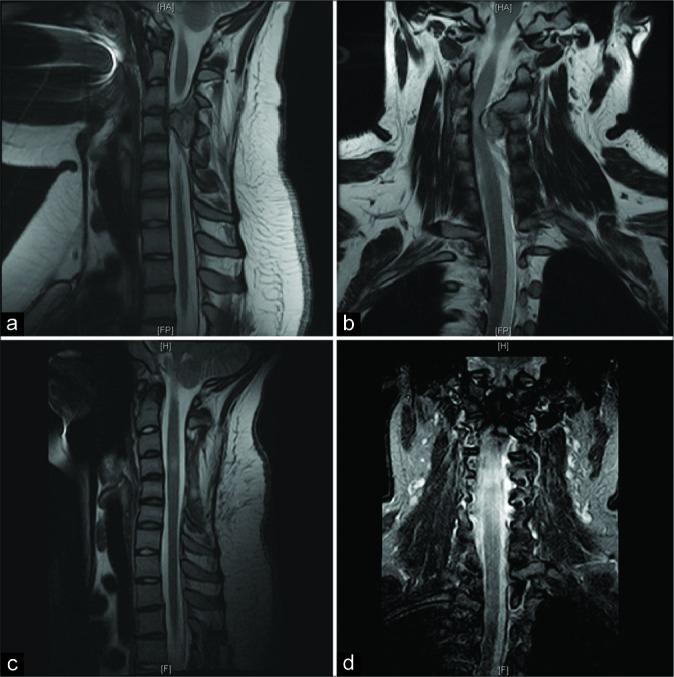

A 15-year-old female presented with a 3-month history of progressive quadriparesis and hand contracture secondary to a magnetic resonance (MR) documented C3-C4 cervical spine osteochondroma. The MR imaging revealed a solitary osseous extramedullary outgrowth arising from the left laminar cortex of the C-3 vertebral body extending to C-4. Due to the marked resultant canal stenosis, the patient underwent a cervical laminectomy of C3- C4 with posterior spinal fusion. Gross total resection was achieved, and the pathology confirmed an osteochondroma. The patient's myelopathy resolved, and 2 years later, she demonstrated no residual deficits or tumor recurrence.

一名15岁女性,有3个月进行性四肢瘫和手部挛缩病史,磁共振成像(MR)显示为C3 - C4颈椎骨软骨瘤。MR成像显示一个孤立的髓外骨性突起,起源于C3椎体左侧椎板皮质,延伸至C4。由于明显的椎管狭窄,患者接受了C3 - C4颈椎椎板切除术及后路脊柱融合术。实现了肿瘤全切,病理证实为骨软骨瘤。患者的脊髓病得到缓解,2年后,她没有残留神经功能缺损或肿瘤复发。